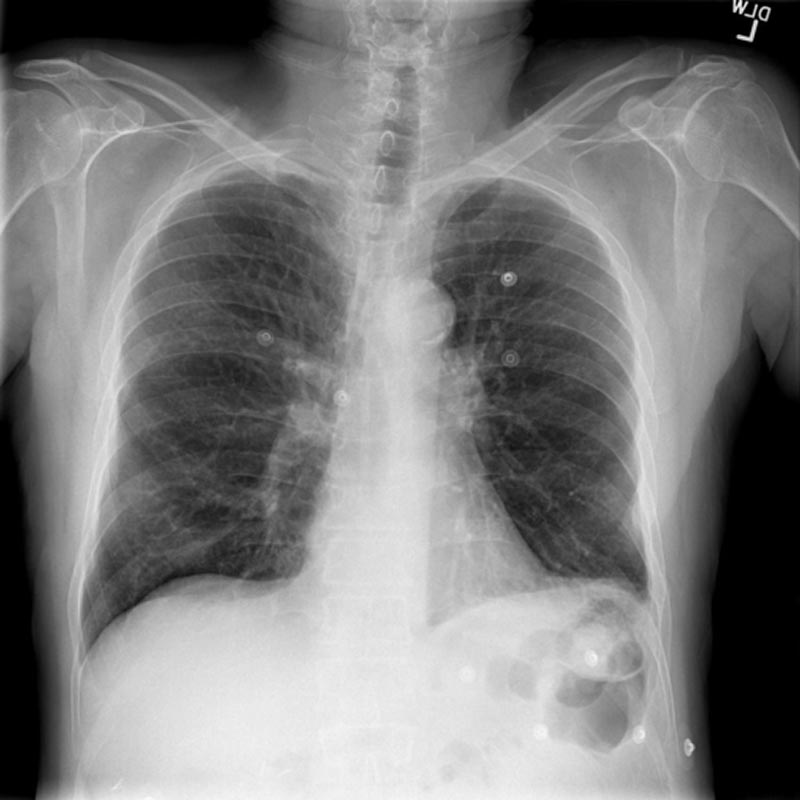

This is a 55-year-old female with a history of CHF and COPD who presents with cough and shortness of breath for 3 days. She is found to have a COPD exacerbation. Her bedside ultrasound shows normal cardiac function and no pulmonary edema, so she is treated with nebs and steroids. Learners should be able to distinguish between a CHF exacerbation and COPD exacerbation using ultrasound and manage the COPD exacerbation effectively.